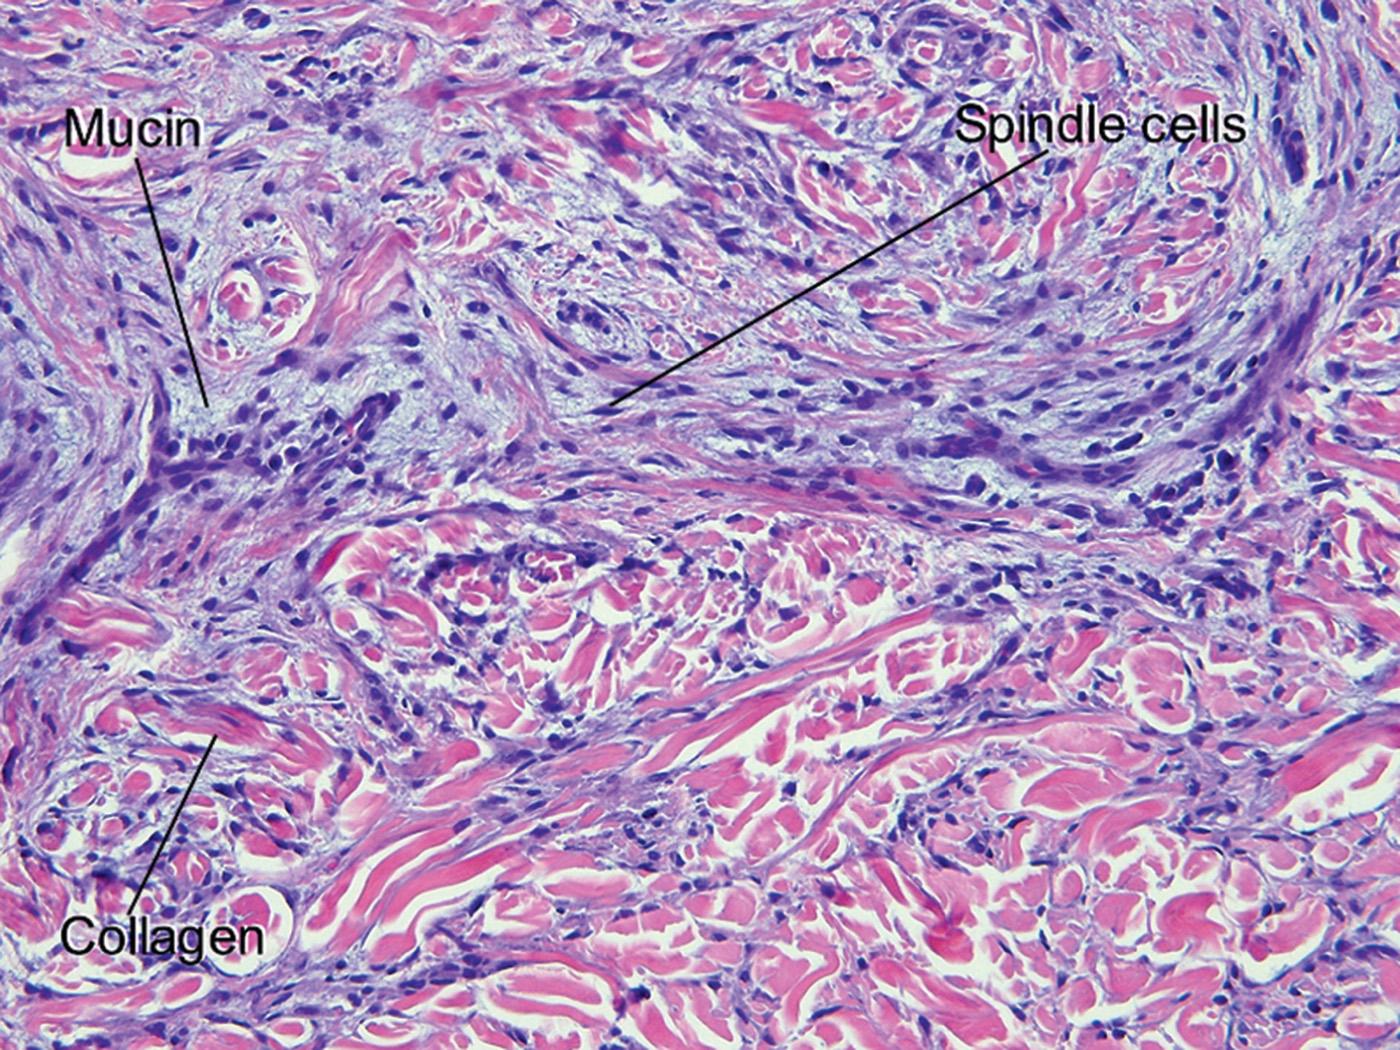

Fig. 14.5, Scleromyxedema

Fig. 14.6, Scleromyxedema

• Increase in dermal fibroblasts, fine collagen fibers, and interstitial mucin

Papular mucinosis (lichen myxedematosus) is composed of linear arrays of waxy papules. Scleromyxedema is a variant in which the papules coalesce with diffuse sclerosis of the skin. An immunoglobulin (Ig) G lambda gammopathy is associated with scleromyxedema and many cases of papular mucinosis.